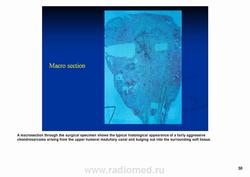

С диагностической точки зрения хондросаркомы подразделяют на хондросаркомы низкой (I), средней (II) и высокой (III) степени злокачественности. Почти 60–90% хондросарком относится к хондросаркомам низкой и средней степени злокачественности.

Рентгенологически выявляют в очаге деструкции участки обызвествления в виде крапчатости; кортикальный слой с признаками эрозии со стороны эндоста и истончения; размеры опухоли более 4 см; периостальная реакция слабо выражена или отсутствует; может наблюдаться деструкция кортикальной кости и наличие мягкотканного компонента; в длинных костях локализуется чаще в метафизах и диафизах; интенсивное внутрикостномозговое распространение.